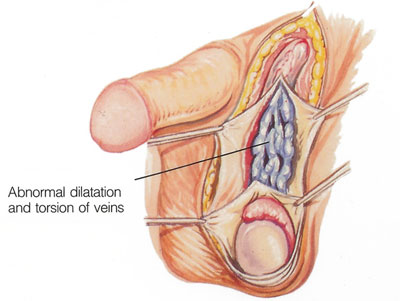

وفي التورم الدواليّ في الصفن Varicocele ينتج التورم من الاوردة المتضخمة (الدوالي) الخارجة من الخصيتين.

وفي حالة التورم الدواليّ قد تحس بالادورة المتضخمة من خلال الصفن، وقد يظهر التورم وختفي بشكل متكرر، وعادة مايزيد عند وقوفك.

ودالي الخصية يمكن أن تقلل خصوبتك لأن الاوردة المتضخمة تمنع وصول الحيوانات المنوية من الخصيتين الى السائل المنوي، ولكنها لا تؤثر على القدرة على الانتصاب. فإذا كانت حالة الدوالي تعوق خصوبتك، فإطلب من طبيبك أ، يحولك إلى جراح ليقوم بربط الادورة المتضخمة.